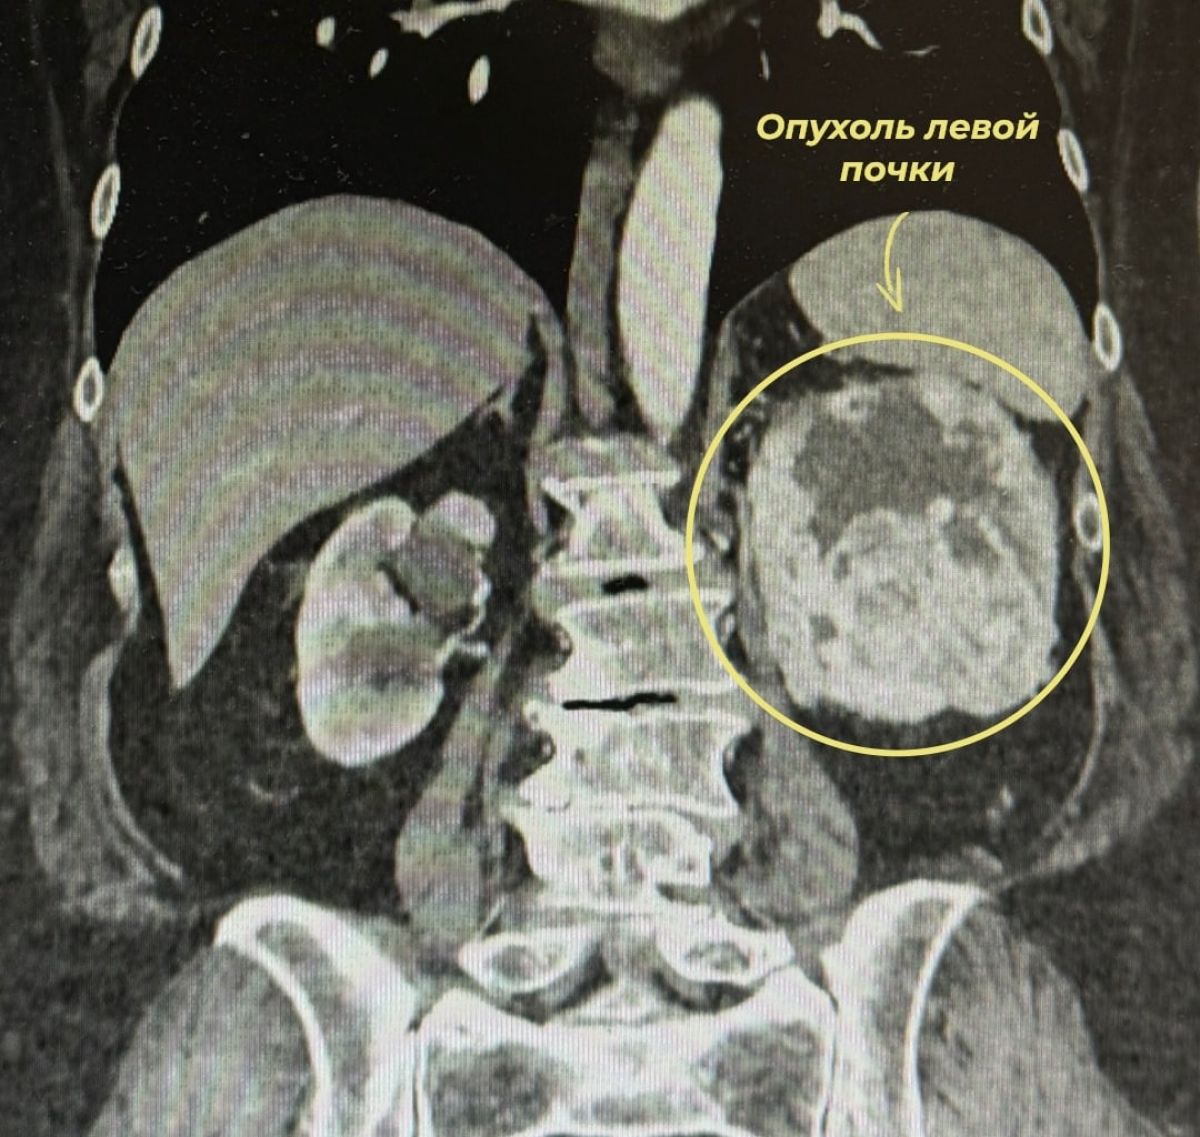

В администрации медучреждения сообщают, женщина обратилась к врачам с жалобами на тянущие боли в пояснице и появление крови в моче. После дополнительного обследования у неё обнаружили злокачественную опухоль левой почки.

Как пояснили специалисты, опухоль оказалась крайне сложной – по специальной шкале оценки она получила максимальные 10 баллов. Это означает высокий уровень сложности для хирургического лечения.